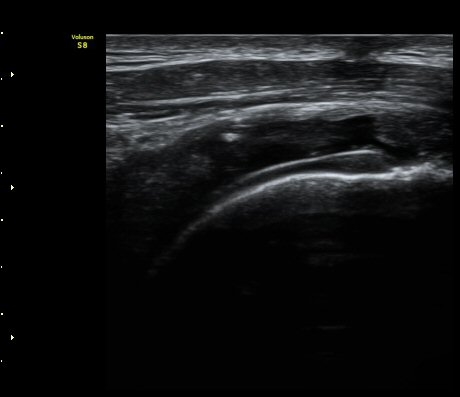

°ß°©ÇÏ±Ù°Ç Á¾´Ü¸é°Ë»ç¿¡¼­ ÀÌ»ó ¼Ò°ßÀ» º¸ÀÌÁö ¾Ê´Â´Ù(»çÁø 2)